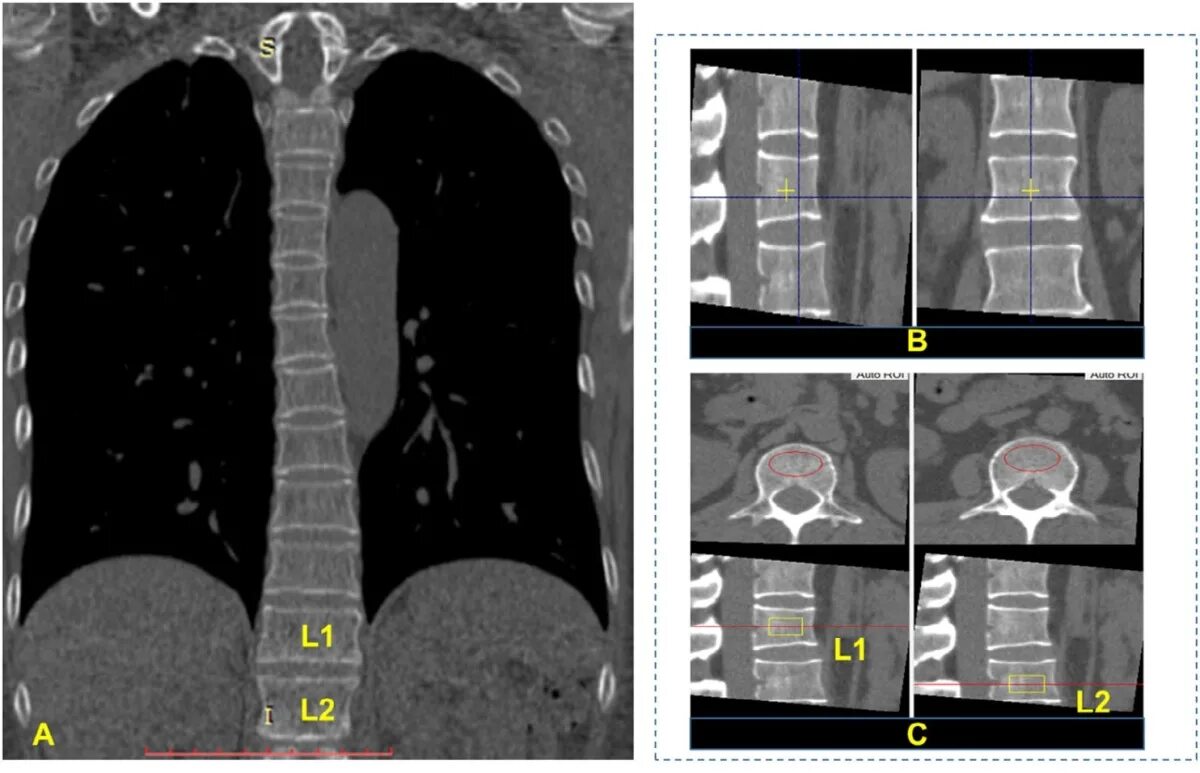

Скрининг кт